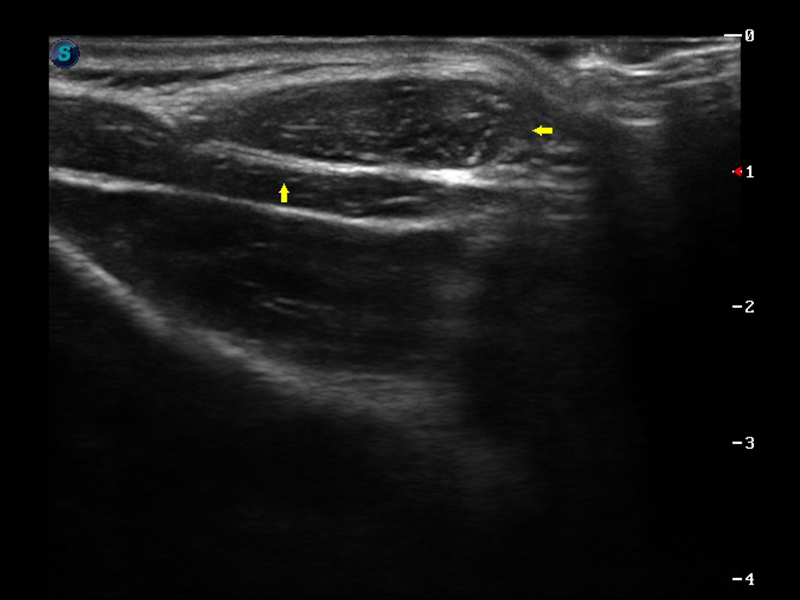

S9便携式彩色多普勒超声诊断仪是亚星官网研发的高端便携彩超设备,外观设计新颖、产品性能卓越。S9在便携超声领域采用了突破传统的触摸屏交互设计,并以先进的软件硬件技术和设计理念,为您带来清晰的图像质量、稳定的工作性能和便捷的操作体验。